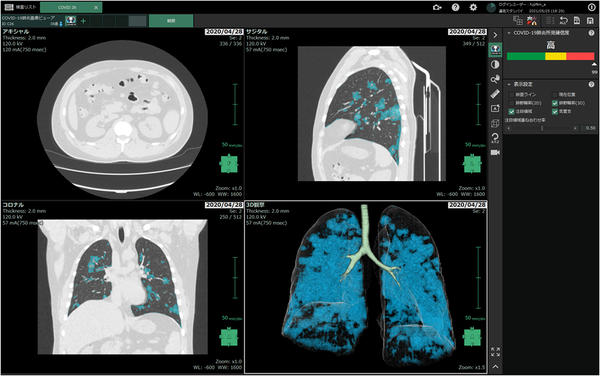

「COVID-19肺炎画像解析プログラム」画面イメージ

右上にCOVID-19肺炎所見を含む可能性(確信度)を三段階で表示。また,確信度の判定に寄与した領域を水色でマーキングする。アキシャル(体を水平に切断)・コロナル(体を前後に切断)・サジタル(体を垂直に切断)の三断面および3Dで表示が可能。